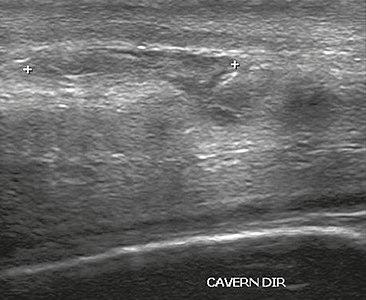

Ultrasound examination is able to depict the tunica albuginea tear in the majority of cases (as a hypoechoic discontinuity in the normally echogenic tunica). In a study on 25 patients, Zare Mehrjardi et al. concluded that ultrasound is unable to find the tear just when it is located at the penile base. In their study magnetic resonance imaging (MRI) accurately diagnosed all of the tears (as a discontinuity in the normally low signal tunica on both T1- and T2-weighted sequences). They concluded that ultrasound should be considered as the initial imaging method, and MRI can be helpful in cases that ultrasound does not depict any tear but clinical suspicions for fracture are still high. In the same study, authors investigated accuracy of ultrasound and MRI for determining the tear location (mapping of fracture) in order to perform a tailored surgical repair. MRI was more accurate than ultrasound for this purpose, but ultrasound mapping was well correlated with surgical results in cases where the tear was clearly visualized on ultrasound exam.[10] The advantage of ultrasound in the diagnosis of penile fracture is unrivaled when its noninvasive, cost-effective, and nonionising nature are considered.[11]

In the ultrasound examination, a lesion of the tunica albuginea presents as an interruption in (loss of continuity of) the echoic line representing it (Figure 4). Small, moderate, or broad hematomas demonstrate the extent of that discontinuity. Intracavernous hematomas, sometimes without the presence of a tunica albuginea fracture, can be observed when there is a lesion of the smooth muscle of the trabeculae surrounding the sinusoid spaces or the subtunical venular plexus.[2]